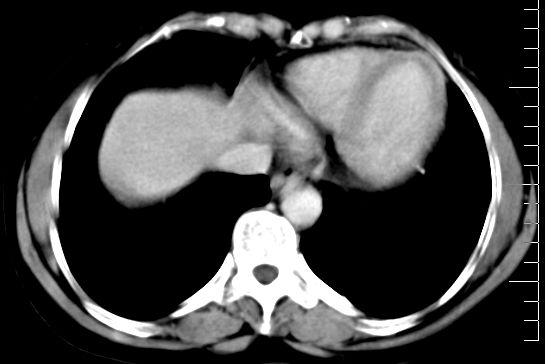

肝大小形态未见异常,肝内外胆管无扩张,肝s8段见一动脉期明显血管样强化结节,门脉期呈高密度,延迟期呈等密度,胆囊不大,增强扫描见胆囊及胆囊颈管壁增厚,有强化。